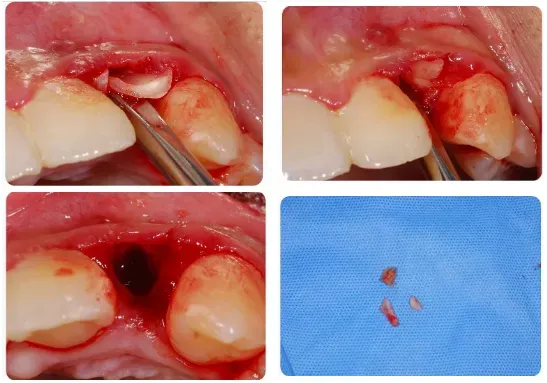

●通过图片和视频讲解各类下颌阻生第三磨牙的微创拔除方法

5、复杂的多根牙和单根牙也可以“简单”拔除;

●通过微创方法解决复杂的单根牙、多根牙

●小断根处理的新思路和注意事项